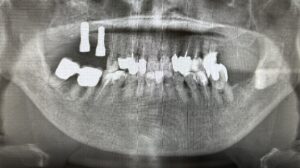

そもそもインプラントは失った歯を自分の歯の代わりとして人工の歯根を顎の骨に埋め込み、その上に人工の歯を装着して噛み合わせを回復する治療法です。

上の歯が難しいとされている大きな要因は下記の通りです。

【歯根部の硬さの問題】

・顎の骨は、皮質骨と海綿骨で構成されている

・上顎は下顎よりも海綿骨の比率が高い

・歯根部を埋入するための硬さがやや不足しているケースが多い

【骨密度の問題】

・上顎は下顎に比べて骨密度が低い

・顎の骨に埋入した歯根部の結合に時間がかかる

・上記の理由から上の歯はインプラント治療が難しい

【副鼻腔の問題】

・顎の骨が薄いケース

・切歯管内の組織を巻き込まないように注意しなければならない

・インプラント周囲炎を起こすと上顎洞炎の原因になる

上の歯のインプラントが難しいか、ご理解いただけたかと思います。

ご不安なことも多いかと思いますが、当院では、これまで数多くの上の歯のインプラントを実施してきました。